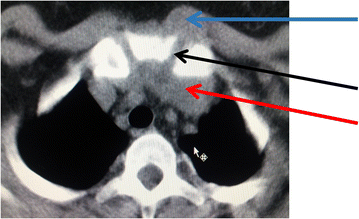

Chest X-ray showed reticular and nodular opacities disseminated throughout the lung fields (Fig. 3). The ultrasound of the sternoclavicular joint revealed regional fluid collection. Chest CT-scan showed small nodules in the parenchymal lungs windows resulting in tree-in-bud sign. Pre and retrosternal collections throughout the joint were observed in the mediastinal window. Bone window showed irregular bone surfaces on the sternoclavicular joint as a result of erosion process suggesting an arthritis.

After 2 months post therapy the patient’s symptoms completely disappeared with complete resolution of the lesion. CT scan showed complete healing of the lesion after 9 months of treatment (Fig. 4).